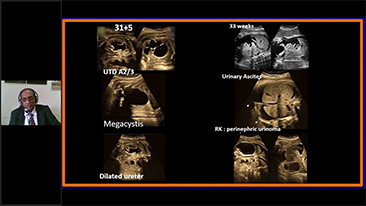

Geoptimaliseerde workflows in gynaecologie en verloskunde zijn noodzakelijk ter ondersteuning van grote pati?ntenvolumes aan screeningbezoeken voor vrouwen. Misvormingen van het centrale zenuwstelsel (CZS) zijn bijvoorbeeld een van de meest voorkomende aangeboren afwijkingen. Als gevolg van verschillende beeldvormingscondities, zoals een slechte foetale positie, is de MSP zeer moeilijk te vinden in een 2D-echografie. Daarom kunnen geautomatiseerde detectie en metingen de scaneffici?ntie sterk verbeteren.